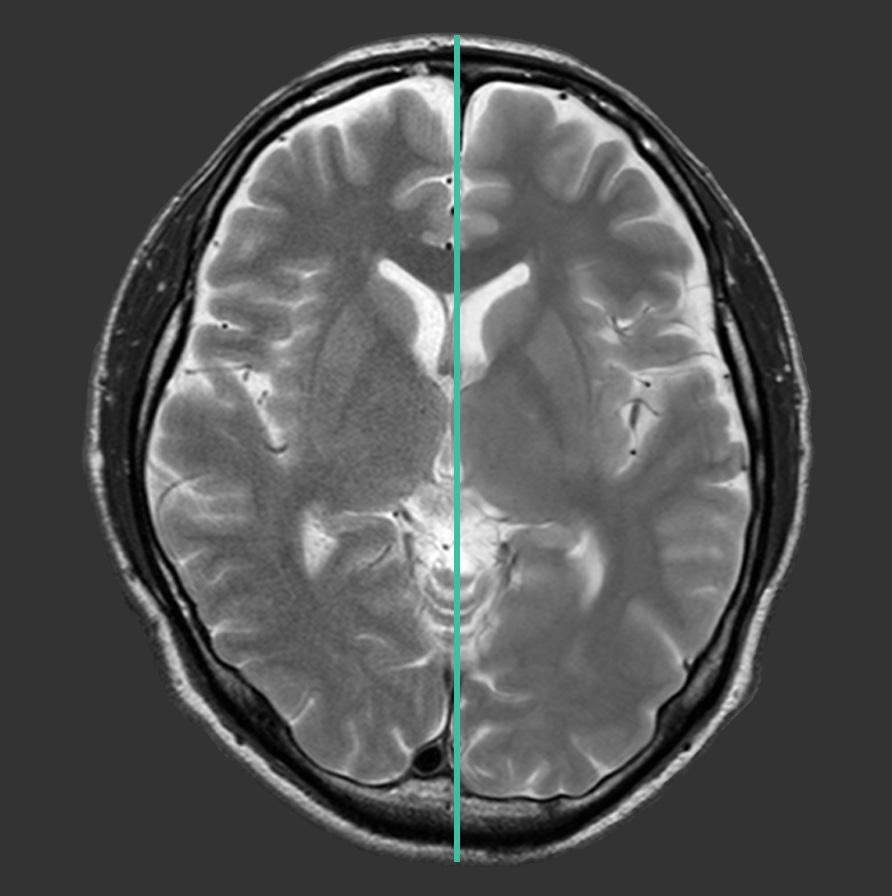

Fujifilm Healthcare Americas Corporation recently launched Version 10 (v10) suite of innovations for Echelon Synergy 1.5T MRI system. Echelon Synergy v10 deploys several cutting-edge technologies, including Synergy DLR Clear, Synergy Vision with StillShot and automated scanning process enhancements.

A recent study found 15-20% of MRI scans require rescan due to patient motion. Synergy Vision, now available for Echelon Synergy MRI, combines multiple in-bore cameras with StillShot artificial intelligence (AI) to mitigate the impact of motion artifacts. StillShot applies AI to correct motion-compromised raw data, referencing real time motion tracking collected during the scan.

Instead of repeating the acquisition, motion can be corrected, providing clearer, more diagnostic images. StillShot helps to streamline workflow for the technologist and provide a better experience for the patient.

The ”Gibbs” or “truncation” artifact has long been an image quality issue with MRI. Radiologists dealt with it or were compelled to call for longer scan time sequences to address it. Synergy v10 brings DLR Clear, a new AI based algorithm to address the truncation artifact, producing images with mitigated artifact without a scan time extension.

“Radial scanning in MRI serves as a common approach to address patient motion, but the technique faced challenges in certain circumstances from unique artifacts. Fujifilm’s v10 software enhancement was designed to help address these challenges,” said Shawn Etheridge, executive director,

modality solutions marketing for Fujifilm Healthcare Americas Corporation. “With v10, technologists can now apply our RADAR radial sequence with our iterative iRCM IP-Recon processing to mitigate spike artifacts, resulting in clear, high-quality images with reduced motion artifact”.

Deep Learning enhanced AutoPose for breast, hip and spine application are added with Echelon Synergy’s v10. AutoPose automatic slice selection, combined with expansion to whole body application for the AutoSet automated table movement capability, and AutoStart automatic scan start on door closure, can save operator steps, enable reduced total exam times, and allow technologists to better focus on patients.